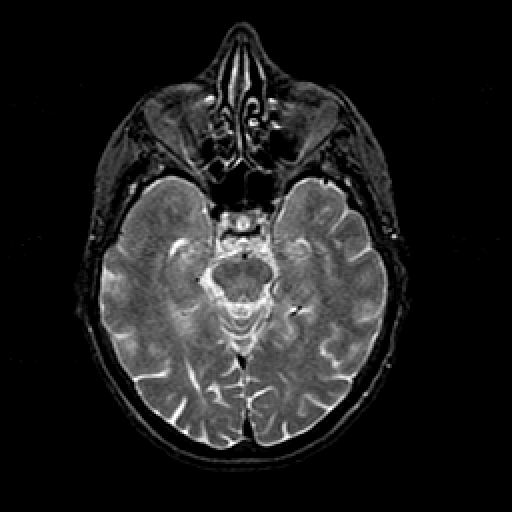

T2-weighted structural MR: Slice 20

Slice 20